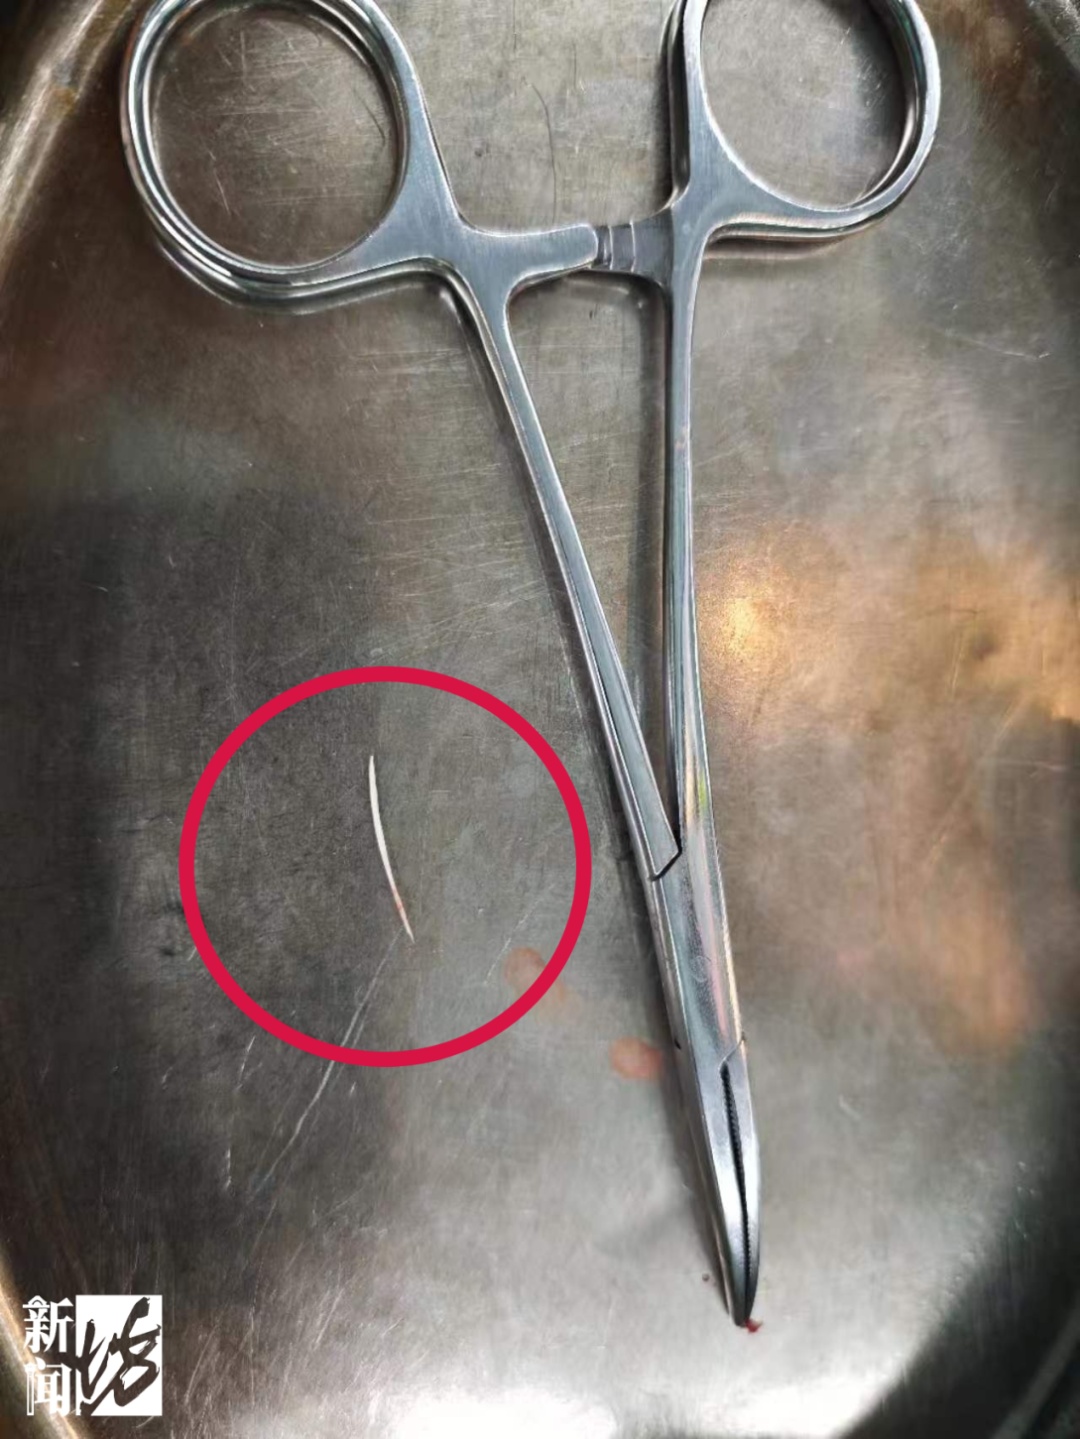

随即,在麻醉科和手术室团队的保障下,张女士被送入手术室。经过细致探查,医生最终在甲状腺左叶上极附近找到并成功取出鱼刺,长度约1.7厘米。随后,手术团队对食管穿孔区域进行规范处理,并清理周围炎性组织,值得一提的是,此次手术仅用了30分钟便顺利完成。